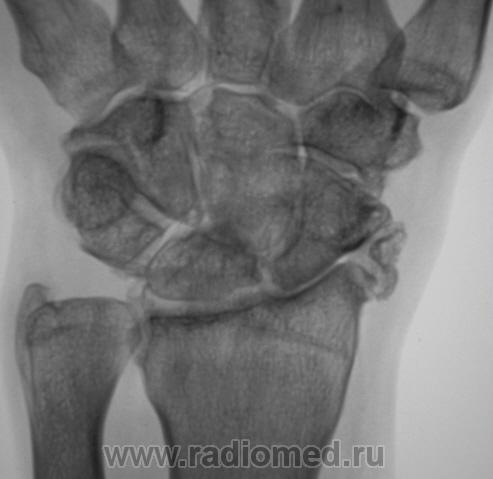

Пациент направлен в рентгеновский кабинет врачом хирургом для рентгенографии лучезапястного сустава. Пациент утверждает, что накануне, имела место быть травма. Произведена рентгенография в стандартных проекциях.

Можно сказать без свежих костно-травматических изменений, веротнее всего посттравматический деформирующий остеоартроз луче-запястного сустава 2ст.(по Н.С. Косинской), да и в межзапястно-пястном суставе так же дегенеративные изменения.

Застарелый отлом фрагмента от шиловидного отростка лучевой кости, деф. артроз л/з сустава.

Cогласен с последним постом.